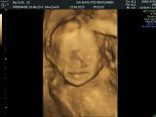

Haii bunda.. Ini hasil USG kemarin waktu UK 22week ?? masih belum jelas bgt karena ketutup lendir lendir kata pak Dokternya. Share juga dong foto2 usg bunda semua ???

Ini hasil USG aku bunda pas usia kandungan 23week baby nya laki laki alhmdulilah semua nya sempurna sehat π